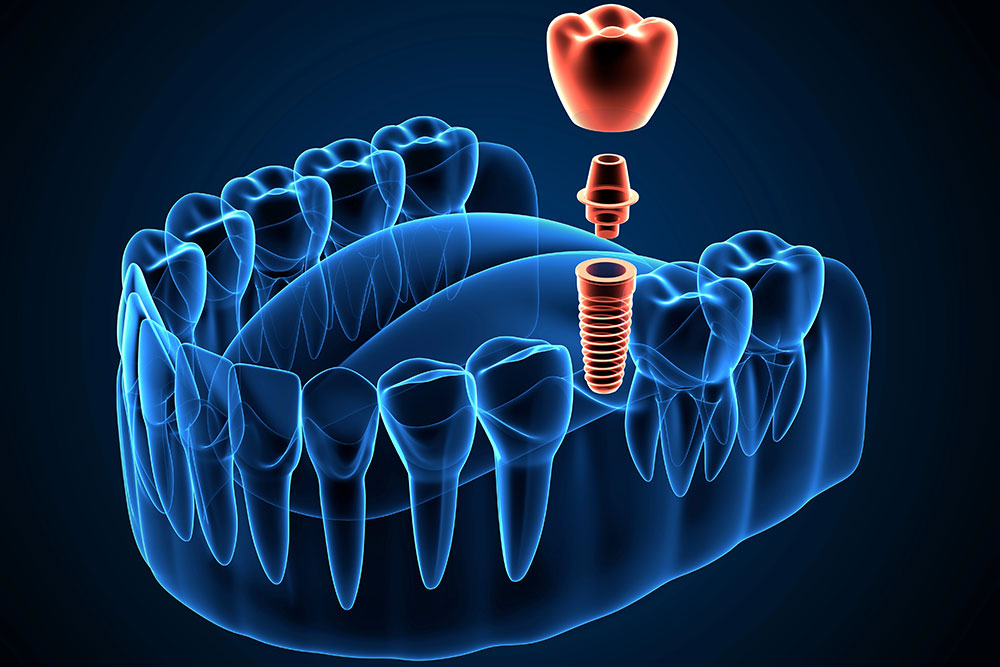

Digital Dentistry And Dental Implants: Trends Transforming The Industry

Placing and restoring dental implants has come a long way. What once required multiple steps, …

New Dental Implant Innovations In 2025

Breakthroughs in implant technology change how dentists restore missing teeth. Dental implant innovations in 2025 …